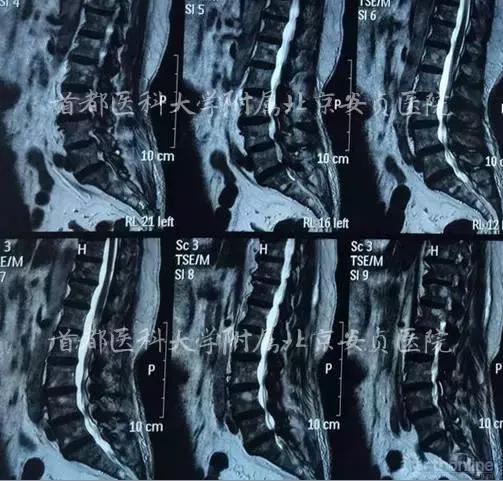

主诉:双下肢麻木无力6个月,颈臂疼痛加重2个月。

现病史:患者6个月前行走时无明显诱因出现双下肢无力、易摔倒、踩棉感,最远可行走50米,伴双上臂外侧疼痛,双侧小腿及足部感觉麻木。胸腹部束带感,无晕厥及意识障碍。近2月感颈后部、双上臂、腰部、骶尾部疼痛、双下肢麻木无力症状加重,行走约20米后出现胸憋气紧,腰背渐前倾不能挺直。

查体:下颈段棘突及椎旁压痛。四肢肌张力不高。双上臂外侧肌肉轻压痛,双侧肱二头肌、桡侧伸腕肌、肱三头肌肌力V级,双手握力V-。双侧Hoffman征(+)。双上肢反射正常。双下肢肌力V级。双侧膝腱反射、跟腱反射亢进,双侧巴氏征阳性。

脊髓型颈椎病、颈椎间盘突出症、腰4滑脱(l度)、腰椎管狭窄、高血压病、冠心病。

本例患者颈4神经根未受累,腹式呼吸未受影响,但患者颈5-6水平脊髓受压,影响患者胸式呼吸,因此患者感到胸闷气紧,吸气无力,说话费力。

本例影像学检查结果示C3-4,C5-6及C6-7均有硬膜囊受压,但是结合症状、体征、高龄,我们选择C5-6为责任节段,进行了针对性的减压,取得了良好的效果。